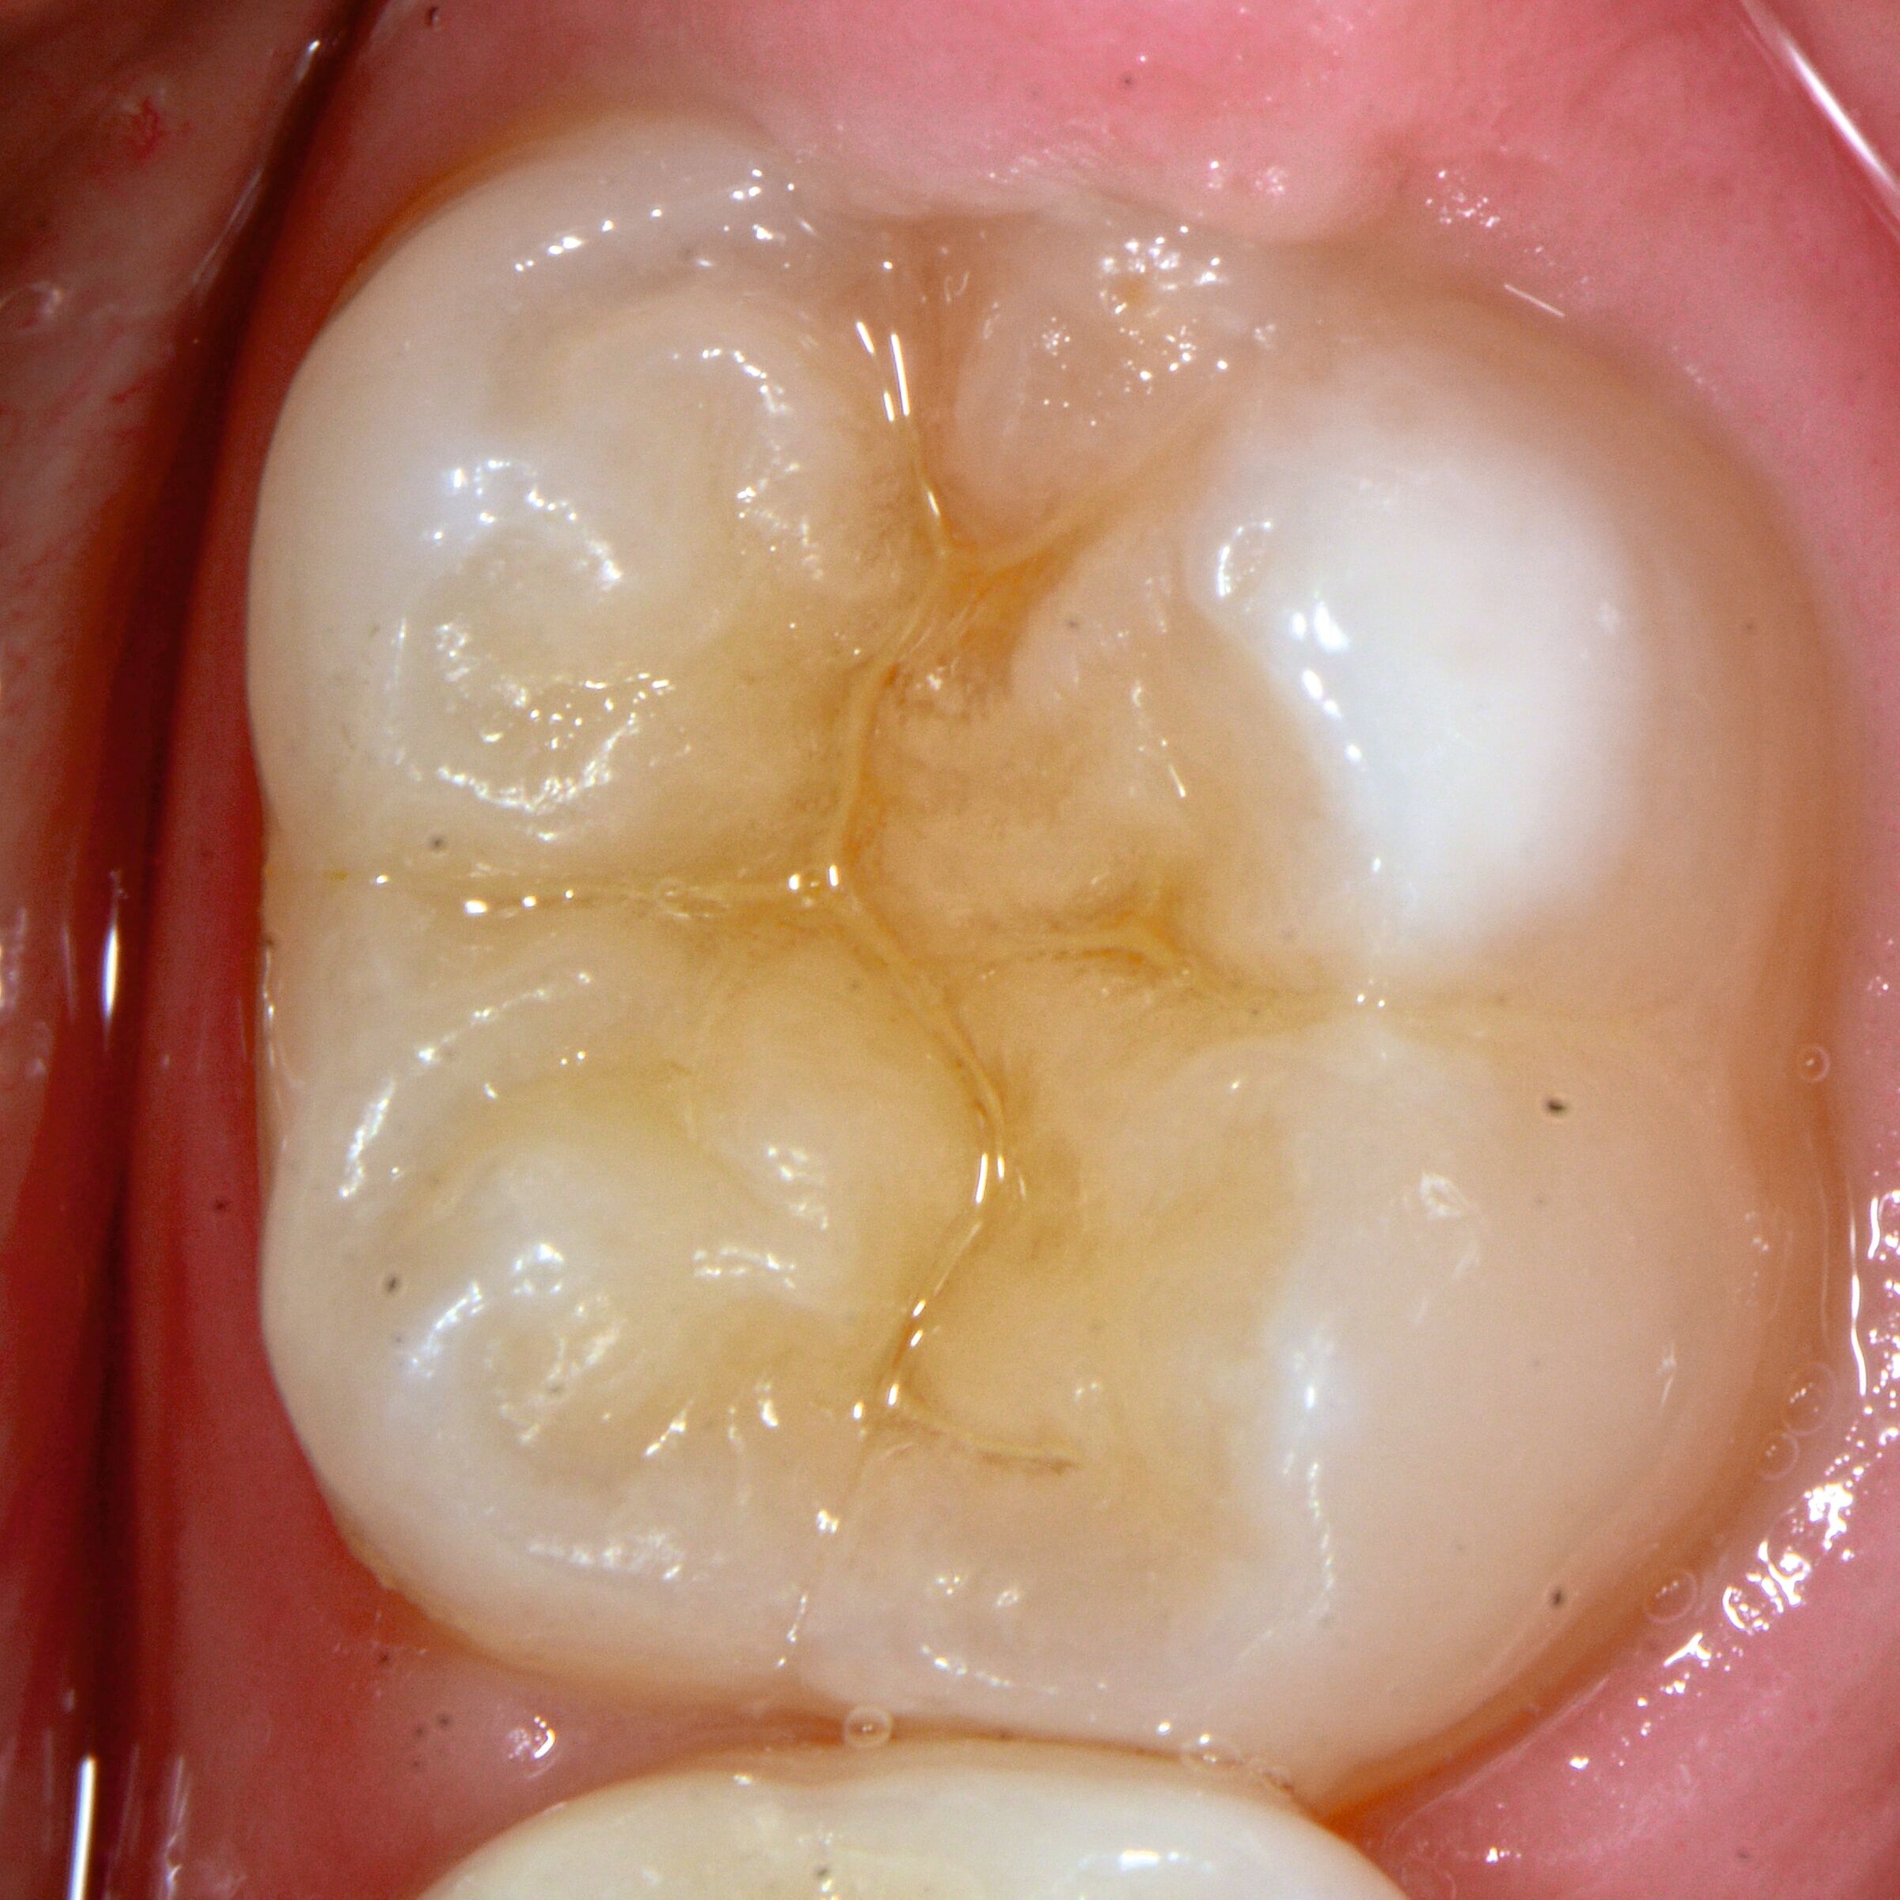

Das klinische Erscheinungsbild an bleibenden Zähnen zeigt typischerweise weißlich-gelbe bis gelblich-braune Opazitäten, die zumindest in einigen Bereichen durch eine scharfe Abgrenzung (engl.:„demarcated opacities“) zum gesunden Zahnschmelz charakterisiert sind (Abbildungen 3 und 4). Die abgegrenzten Hypomineralisationen befinden sich mehrheitlich im Bereich der inzisalen Kronenhälfte unabhängig von dem Auftreten an Front- oder Seitenzähnen. Die Ausprägung am Zahn kann dabei auf einzelne Areale oder Höcker begrenzt sein.

Bei einer schwerwiegenderen Ausprägung sind Zahnflächen vollständig betroffen, mitunter alle Zahnflächen an einem Zahn. Die Verteilung in der Dentition beziehungsweise an den Indexzähnen ist gleichermaßen variabel und betrifft nicht nur die Defektgröße, sondern auch die Farbe und Festigkeit. Was die Festigkeit betrifft, gilt als die Faustregel: Je dunkler die Farbe des Schmelzes, umso weicher beziehungsweise poröser und damit minderwertiger wird dessen Qualität sein. Damit reduziert sich seine kaufunktionelle Belastungsfähigkeit, was insbesondere an ersten bleibenden Molaren von klinischer Relevanz ist.

Für die Dokumentation und Klassifikation der MIH wurden verschiedene Systeme vorgeschlagen. Als historisch und veraltet gilt der (modifizierte) DDE-Index. Demgegenüber haben die Kriterien der EAPD – abgegrenzte Opazitäten (Abbildung 3 und 4), Schmelzeinbrüche (Abbildung 5), atypische Restaurationen (Abbildung 6) – mittlerweile die weiteste Verbreitung gefunden. Diese wurden 2003 erstmals zur Beschreibung der MIH auf empirischer Basis publiziert [Weerheijm et al., 2003] und den Jahren 2010 und 2022 im Rahmen der damaligen MIH-Workshops bestätigt [Lygidakis et al., 2010; 2022].